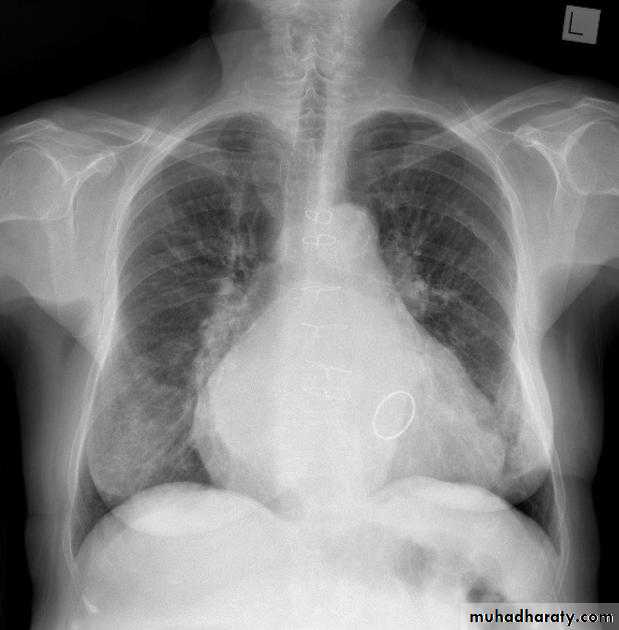

Congestive cardiac failure (CCF) is a form of cardiac failure which is primarily manifested by the heart inability to pump the volume of blood. It can affect the left (common) or right cardiac chambers or both.

Radiographic features

Chest radiograph

With left sided congestive cardiac failure, the features are that of pulmonary edema which includes:

central pulmonary venous congestion ( prominent hilum )

cephalization of pulmonary veins ( upper lobe pulmonary venous diversion )

pulmonary interstitial edema

pulmonary alveolar edema

Cardiomegaly

Pleural effusion